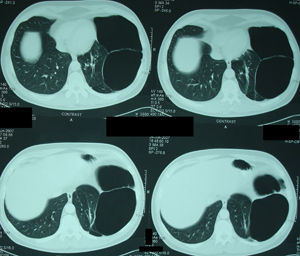

Εικόνα 2α

Αξονική τομογραφία του θώρακος. Τομή στο επίπεδο της κορυφής των

Πνευμόνων. Αερώδεις κύστες που καταλαμβάνουν εξ΄ολοκλήρου το

αριστερό άνω πνευμονικό πεδίο.

Εικόνα 2β

Αξονική τομογραφία θώρακος. Τομή στο επίπεδο της τρόπιδας και στο

ύψος των κυρίων βρόγχων. Πάλι το αριστερό ημιθωράκιο συνεχίζει να

καταλαμβάνεται από αερώδεις κύστες.

Εικόνα 2γ

Αξονική τομογραφία του θώρακος. Τομή στο ύψος της αριστερής κάτω

Πνευμονικής φλέβας. Το αριστερό ημιθωράκιο συνεχίζει να

καταλαμβάνεται από αερώδεις κύστες, ενώ αρχίζει να διακρίνεται πνευμονικό παρέγχυμα.

Εικόνα 2δ

Αξονική τομογραφία του θώρακος. Τομή πάνω από το επίπεδο του

διαφράγματος. Διακρίνεται περισσότερο πνευμονικό παρέγχυμα, ενώ

συνεχίζουν να διακρίνονται αερώδεις κύστες.

Εικόνα 2ε

Αξονική τομογραφία του θώρακος. Τομή στο επίπεδο του διαφράγματος.

Μεικτή εικόνα, αερωδών κύστεων και πνευμονικού παρεγχύματος.